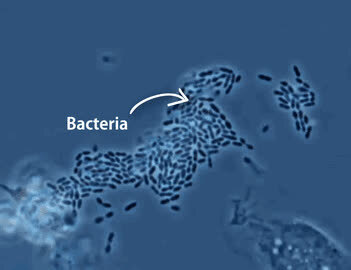

3.这是中性粒细胞追击金黄色葡萄球菌的一个过程。免疫细胞捕捉细菌时是不是超萌!